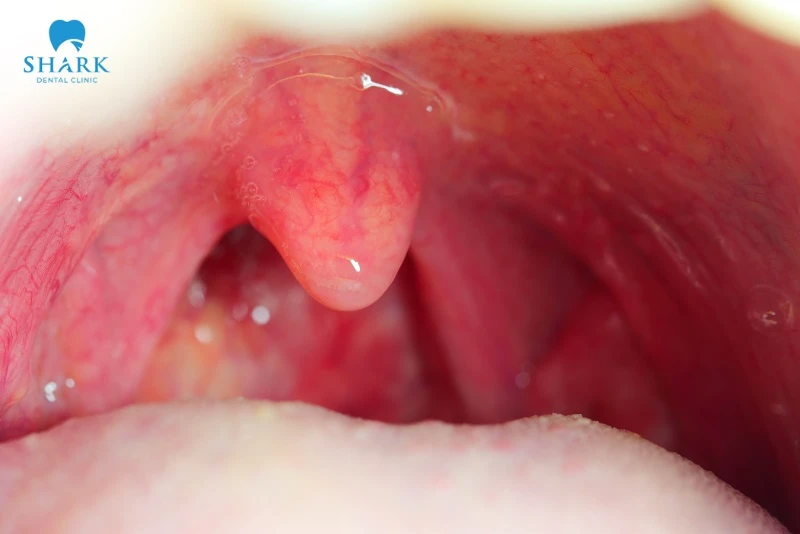

Dấu hiệu và hình ảnh vòm họng bình thường

Việc quan sát hình ảnh vòm họng bình thường thực tế sẽ dựa trên các tiêu chí cụ thể về màu sắc, niêm mạc và cảm giác thực thể.

Màu sắc và niêm mạc

Đây là yếu tố trực quan nhất để đánh giá sức khỏe vòm họng:

- Màu sắc chuẩn: Toàn bộ vùng họng, lưỡi gà và amidan có màu hồng nhạt, không xuất hiện các vùng đỏ rực hoặc tím tái.

- Sự đồng nhất: Màu sắc trải đều từ vòm miệng xuống phía sau thành họng.

- Độ sạch: Bề mặt sạch sẽ, không có đờm nhớt đặc quánh, không có các đốm trắng đục hay vết loét.